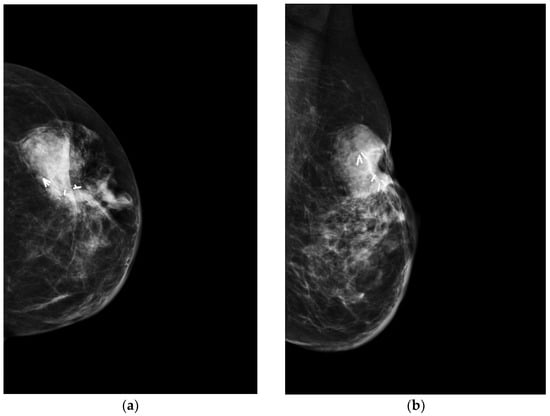

4.1. Mammography